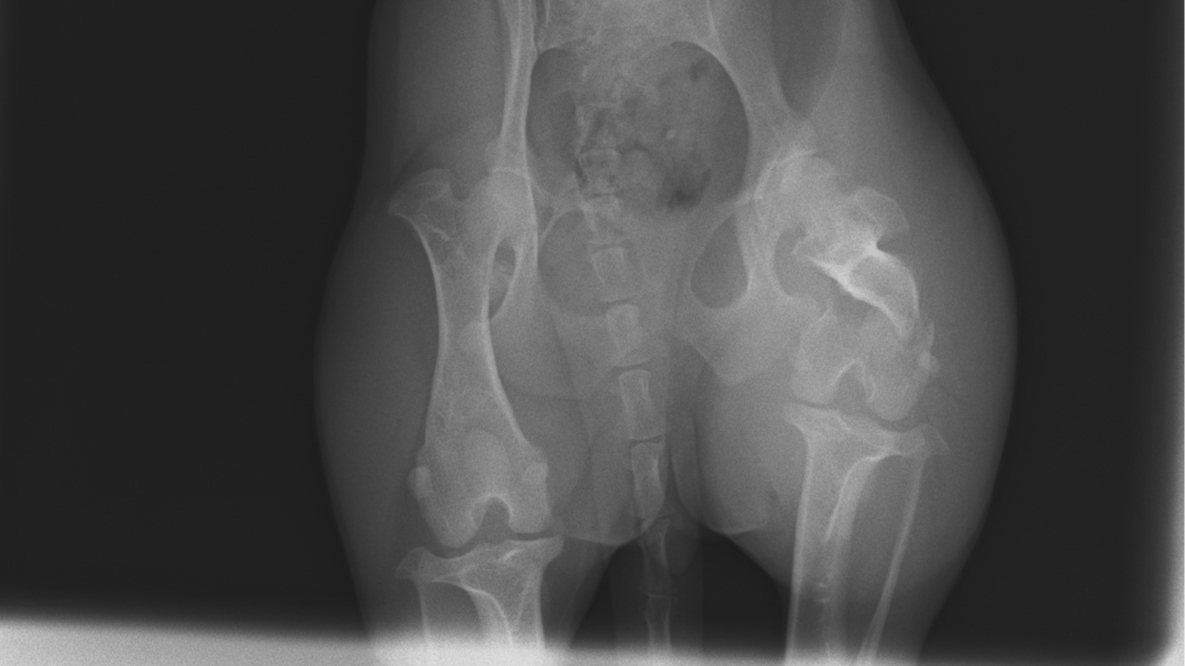

DJ the sausage dog has gotten into an accident and has broken a leg. Het owner is unable to pay for her vet fees to fix it, so she's been taken into the care of Wiener Crew Rescue. The funds raised by you wonderful people will go directly to DJ's vet bill which has been quoted at $6000 We're only a small rescue, and need the help of others in cases like this. We'll share DJ's recovery journey as much as we can. Thank you so much for donating, and please share!